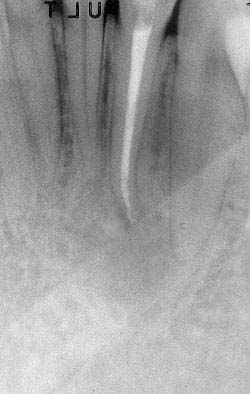

Apertura della corona fino ad arrivare alla camera pulpare (tale trattamento viene eseguito tramite anestesia locale). Si rimuove la polpa e si cercano i canali radicolari del dente, una volta trovati si estirpano i nervi. Si allargano e si puliscono i canali del dente, (tramite strumenti al Nichel titanio o strumenti manuali) prendendo anticipatamente le misure dei canali (per non uscire oltre apice). Si disinfettano i canali e si eseguono vari lavaggi tra un passaggio e un altro per elimininare il fango dentinale. Il medico a questo punto verifica la possibilità di chiudere definivamente i canali o lasciare il dente in prova, inserirendo nei canali un disinfettante e eseguendo una chiusura provvisoria. Al momento di chiudere il dente definivamente, questo viene preparato rieseguendo le misure dei canali da chiudere ed usando per la stessa lunghezza del canale, un cono di guttaperga del diametro necessario. Si scalda il cono in guttaperga e si inserisce nel canale. Durante il trattamento endodondico vengono effettuati una serie di esami radiografici per verificare i risultati, le lunghezze, la forma dei canali.

L'esame radiografico, fondamentale per porre diagnosi in odontoiatria, in endodonzia è irrinunciabile perché è l'unico strumento che ci permette di "vedere" all'interno della radice del dente, è quindi molto importante la possibilità di effettuare lastre con apparecchiature digitali che emettono un quarto della dose di raggi emessa da un radiografico tradizionale e che permettono di conservare la radiografia endorale in una cartella informatica del paziente senza possibili alterazioni nel tempo.